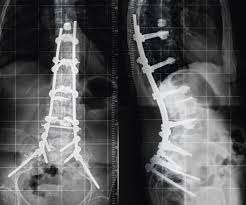

Es kann also schon 2 - 3 Monate dauern bis die Wirbelsäule wieder voll belastungsfähig ist. Weil der Wirbelsäulenkanal der Halswirbelsäule sehr eng ist wird bei der Verletzung in 70 Prozent der Fälle zusätzlich auch das Rückenmark geschädigt. Ob ein operativer Eingriff notwendig ist und welche Art von Operation durchgeführt wird hängt einerseits von der Art des Wirbelbruchs andererseits aber auch von den sonstigen Umständen ab.

Beschreibung Ein Genickbruch bezeichnet einen Wirbelbruch der Halswirbelsäule. Bei einem jungen Sportler ist man eher geneigt eine Operation durchzuführen als bei einem alten bettlägrigen Patienten den man so ohne großen Nutzen für die Dauer von weiteren 2 Monaten in ein. Bei einem Wirbelbruch durch Osteoporose raten viele Ärzte zu einer Operation. Nur 15 bis 20 Prozent aller Wirbelsäulenverletzungen betreffen die Halswirbelsäule. Bei instabilen Brüchen besteht dagegen die Gefahr dass Teile des Bruches die Nervenwurzel im Spinalkanal einengen und dadurch neurologische Ausfälle wie Lähmungen folgen. Weil der Wirbelsäulenkanal der Halswirbelsäule sehr eng ist wird bei der Verletzung in 70 Prozent der Fälle zusätzlich auch das Rückenmark geschädigt. Der erste Halswirbel wird als Atlas bezeichnet der zweite als Axis.